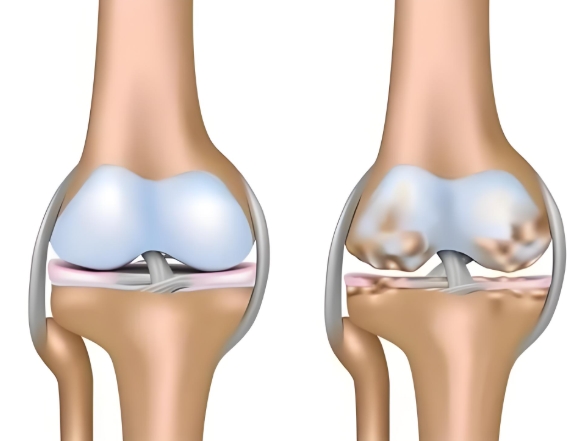

鹽酸和硫酸氨基葡萄糖膠囊都是氨基葡萄糖類藥物,能為關(guān)節(jié)軟骨提供合成原料,在促進(jìn)軟骨基質(zhì)的修復(fù)與再生的基礎(chǔ)上,補(bǔ)充關(guān)節(jié)滑液以減少摩擦,同時(shí)通過(guò)抑制關(guān)節(jié)腔內(nèi)的炎癥因子,從多個(gè)方面幫助延緩骨關(guān)節(jié)炎的進(jìn)展[1],但它們?cè)谂R床療效上卻存在一定差異。

根據(jù)國(guó)際醫(yī)學(xué)四大期刊之一《美國(guó)醫(yī)學(xué)會(huì)雜志》上發(fā)布的一項(xiàng)研究表明,硫酸氨基葡萄糖在緩解膝骨關(guān)節(jié)炎疼痛、改善關(guān)節(jié)活動(dòng)功能方面,效果優(yōu)于鹽酸氨糖等33種骨關(guān)節(jié)炎常用藥[2]。還有相關(guān)研究顯示,硫酸氨基葡萄糖不僅能延緩關(guān)節(jié)間隙變窄,還能從根源改善關(guān)節(jié)結(jié)構(gòu)、減緩磨損。而鹽酸氨基葡萄糖在這一關(guān)鍵指標(biāo)上的效果尚未明確。因此,在關(guān)節(jié)保護(hù)的“確切性”上,硫酸氨基葡萄糖顯然更具優(yōu)勢(shì)。

硫酸氨基葡萄糖膠囊中含有的硫酸根是人體關(guān)節(jié)軟骨中蛋白聚糖的天然組成成分。這種與人體兼容的“內(nèi)源性”特質(zhì),讓它口服后吸收利用率可達(dá)90%[3]。而且對(duì)胃腸道會(huì)更溫和,耐受性更佳。反觀鹽酸氨基葡萄糖膠囊,它所含的氯離子不是關(guān)節(jié)正常代謝所需,可能會(huì)在口服后刺激胃腸道黏膜[4]。這種刺激不僅會(huì)引起腸道不適,還會(huì)干擾藥物在腸道的吸收,降低其生物利用度。